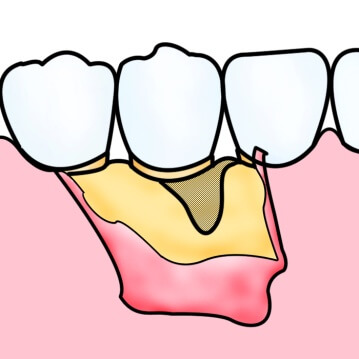

歯周病の進行により、歯を支えている骨は溶けてしまいます。通常、一度失った骨は元に戻りませんが、ケースによっては再生療法によって骨の回復が可能となります。また、平成28年9月に、厚生労働省より承認を受け、最近、保険導入された、歯周組織再生剤「リグロス®」の使用も行っております。(その他にもいくつかの方法があります。)

歯周病によって失ってしまった歯周組織部位に、歯周組織再生剤を塗布することで骨組織を再生させます。